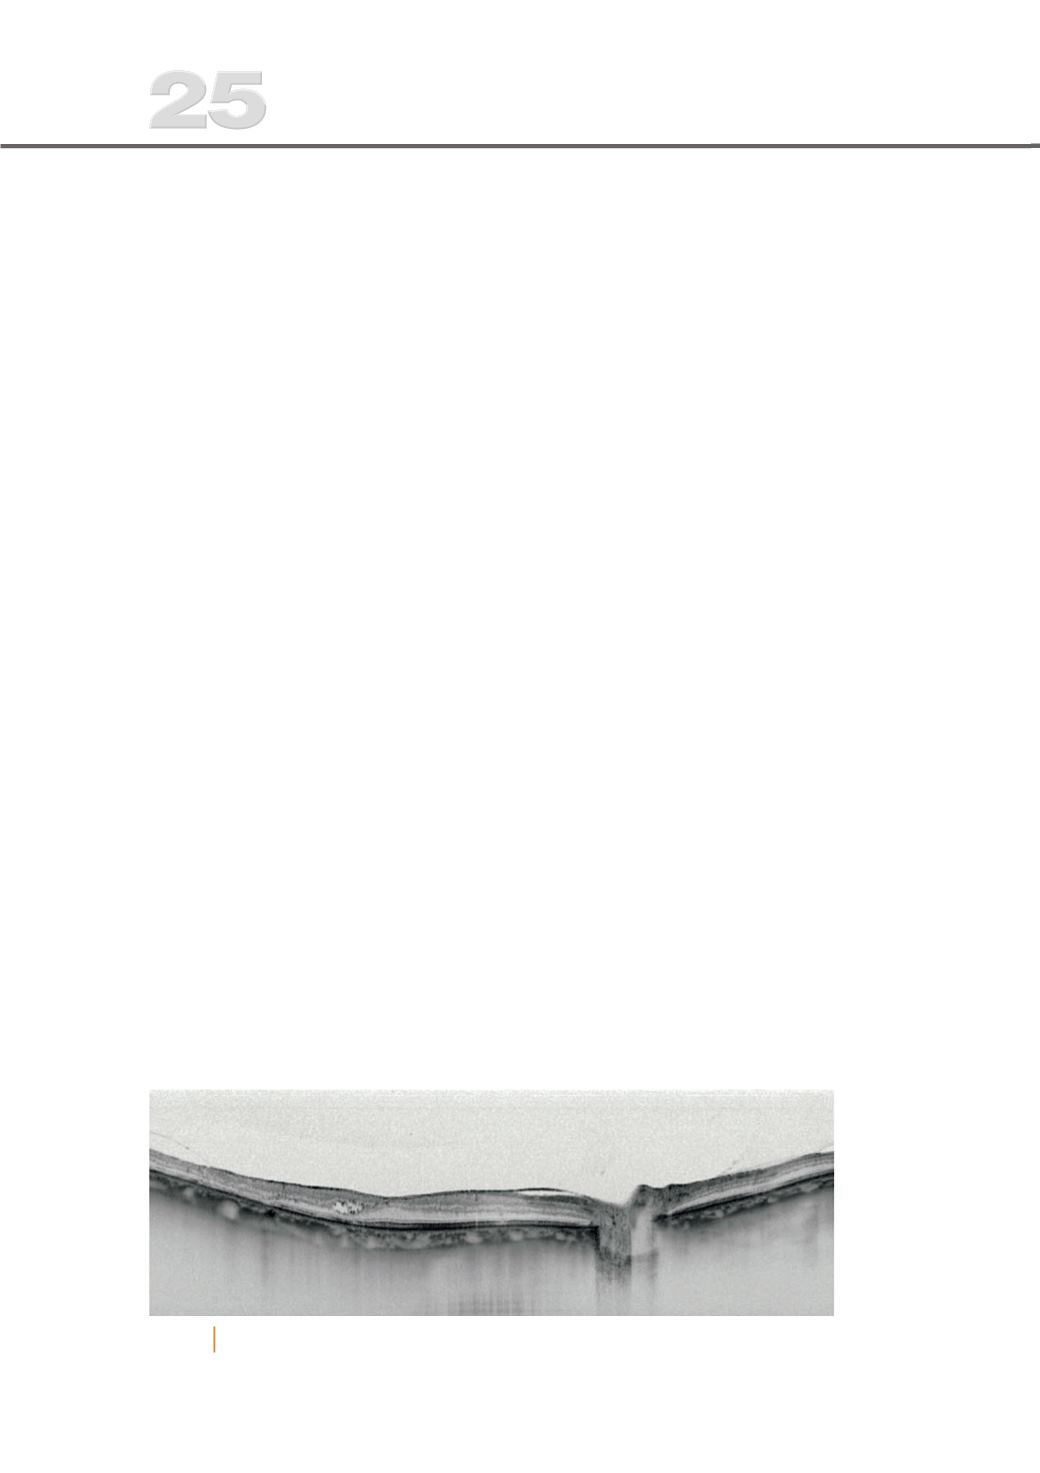

Fig. 3

EMD com tração vítreomacular; irregularidades dos vasos coroideus